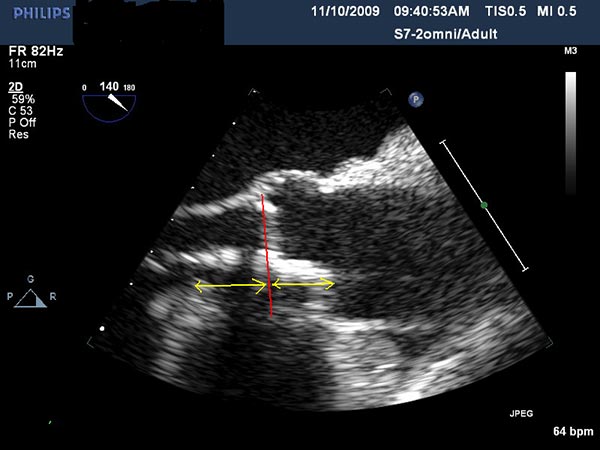

- The Sapien valve is then delivered through the introducer sheath and positioned across the aortic annulus with 50% of the valve above the annulus and 50% below the annulus. Both TEE and aortic root injection are used to confirm the position of the valve and its spatial orientation. Ideally, the valve should be in line with the long axis of the ascending aorta and perpendicular to the aortic annulus (Figure 3, 4, 5).

Figure 3. Direct echocardiographic visualization of the left ventricular outflow tract during valve insertion.

- After deployment, both TEE and another angiographic root injection are performed to confirm the position of the valve (Figure 7, 8), rule out paravalvular or central leak and to confirm the patency of the coronary arteries. Occasionally, the valve may require an additional insufflation with additional saline.